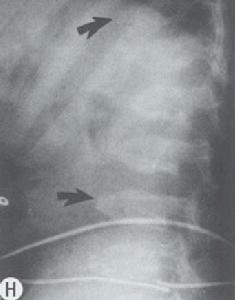

2.對胎兒新生兒的影響本病孕婦出生的嬰兒有發生甲狀旁腺功能亢進症的報導其原因是母體血鈣低,向胎兒移行的鈣減少,胎兒血鈣低刺激甲狀旁腺呈過度增生,使PTH分泌亢進所致。在出生後1周的新生兒,X線攝片可見鎖骨、腕骨、下肢和大腿骨的骨膜下皮質重吸收相及囊狀纖維性骨炎,以及大腿骨骨幹端緣骨折等。可有胎死宮內及新生兒死亡未見致胎兒畸形的報導。手術後者大多孕前已獲診斷及治療,新生兒一般均正常。